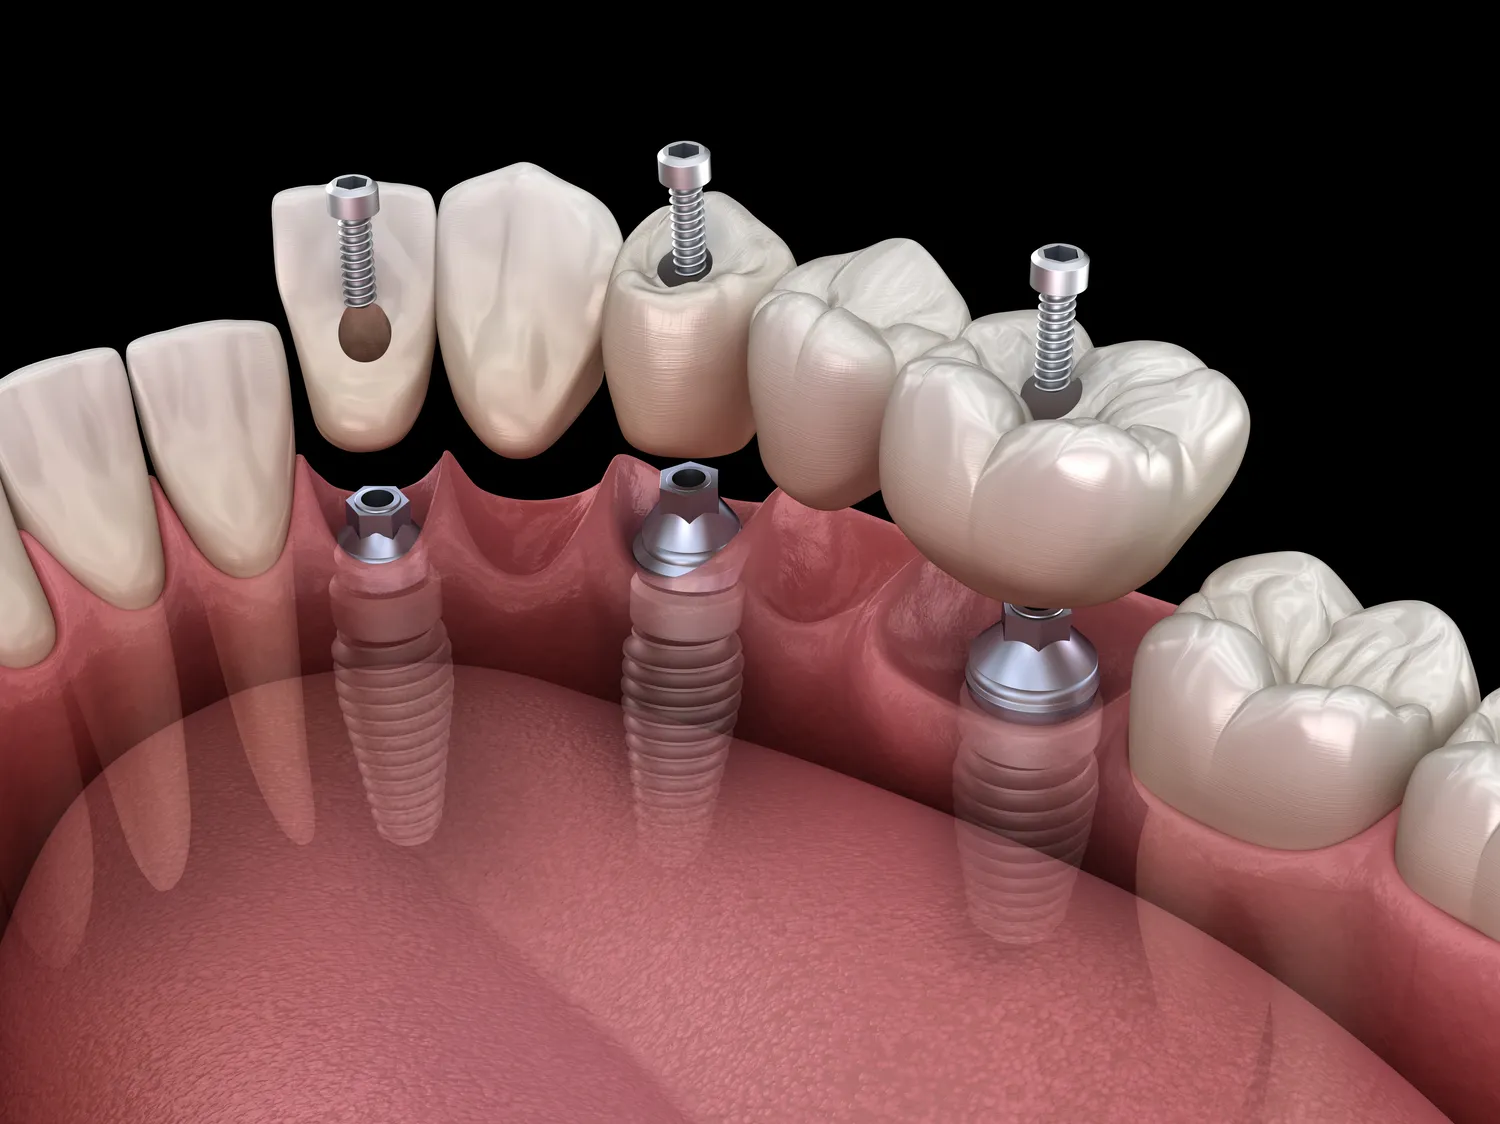

Proces wszczepienia implantów zębowych w Polsce składa się z kilku kluczowych etapów, które są starannie zaplanowane, aby zapewnić pacjentowi jak najlepsze rezultaty. Pierwszym krokiem jest konsultacja stomatologiczna, podczas której lekarz ocenia stan uzębienia pacjenta oraz wykonuje niezbędne badania, takie jak zdjęcia rentgenowskie. Na podstawie tych informacji lekarz podejmuje decyzję o możliwości wszczepienia implantu oraz planuje dalsze kroki. Kolejnym etapem jest przygotowanie do zabiegu, które może obejmować leczenie chorób przyzębia czy przeszczep kości, jeśli to konieczne. Sam zabieg wszczepienia implantu odbywa się w znieczuleniu miejscowym i polega na umieszczeniu tytanowego implantu w kości szczęki lub żuchwy. Po zabiegu następuje okres gojenia, który trwa od kilku tygodni do kilku miesięcy; w tym czasie implant integruje się z kością. Ostatnim krokiem jest zamocowanie korony protetycznej na implancie, co przywraca funkcjonalność i estetykę uśmiechu pacjenta.